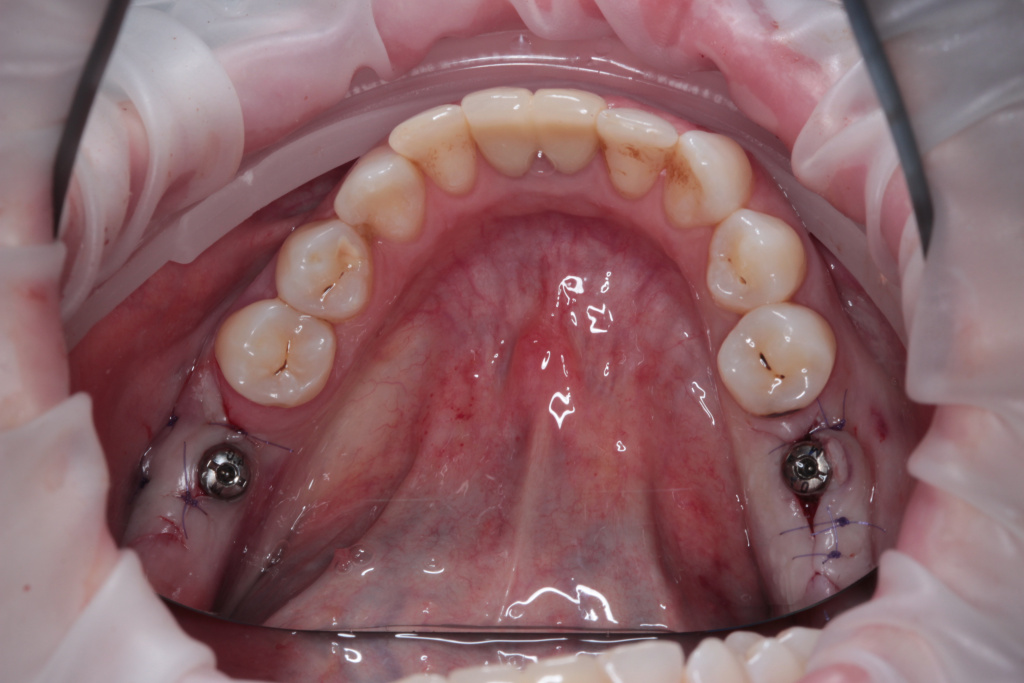

- Атравматичное удаление

- Пластика десны

- Имплантация IMPRO

- Ушивание раны